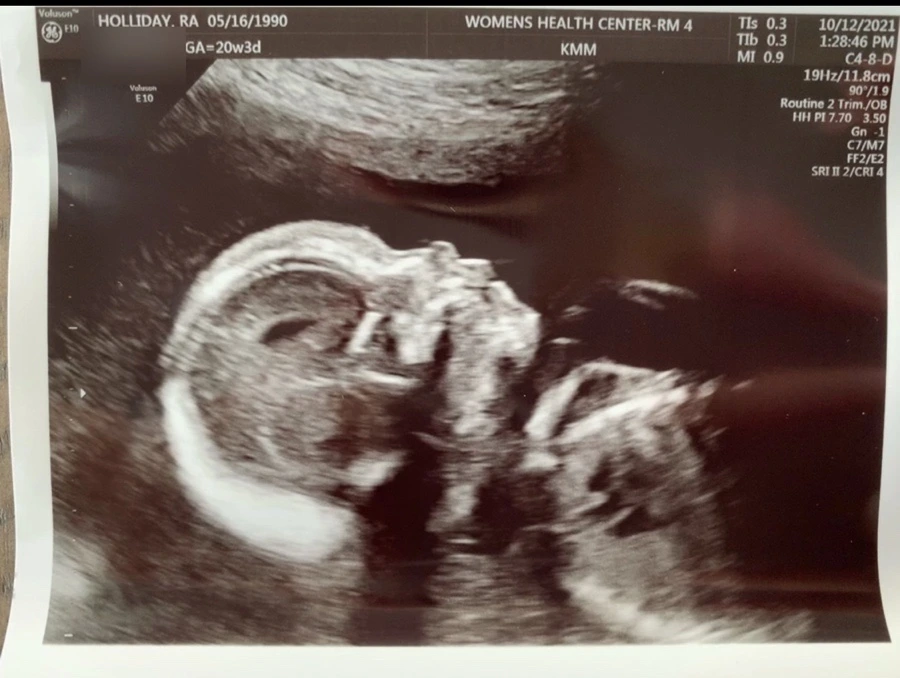

이 이야기를 써야 할지 말아야 할지, 어디서부터 시작해야 하나 임신 기간 내내 고민을 했다. 원망도 아니고 슬픔이나 우울함도 아니다. 새로운 경험이니까 글로 남겨두기로 한다.

성인이 되고 나니 스무 살의 미성년자를 벗은 나도 어른이 아니었고, 결혼을 하고 나니 그전의 나는 더더욱 어른이 아니었고, 집을 사는 과정을 지나보니 여전히 나는 어른이 필요했고, 아이를 가지고 보니 더더욱 어른은 간절하다. 심지어 20살 이후로도 그런데 그전의 나는 혼자서도 알아서 잘 한다는 말로 어른이어야 했던 아이 같다고 느꼈다. 내 어린 시절이 애잔했다. 나는 아이를 갖은 건데 왜 내 어린 시절의 모습이 보이는 걸까. 내가 마주하고 싶다고 한 것도 아닌데 누군가 옛다 여기있다, 네 어린시절의 기억들! 이라며 보따리 채 던져 주었던 시간들 같았다. 아이를 갖는다는 건, 그 과정 속에 내가 겪을 일들은 몸의 변화만은 아니었다. 임신은 베일에 쌓인 이야기 같다. 아무도 이야기 해주지 않는, 오롯히 혼자 겪어 가다보면 그제서야 하나 둘 이랬었지 입에서 입으로 구전으로만 전해지는 이야기.